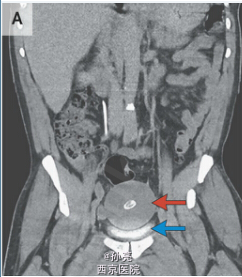

腹部和骨盆CT显示有一个中线为8.5cm长的肿块,伴有中心钙化(图A,红色箭头),在膀胱上方并压迫膀胱(图A,蓝色箭头)。腹腔镜探查显示一个游离、光滑、坚硬且有弹性,大小为10cm×9.5cm×7.5cm,重220克的肿块(图B和图C)。切片标本包含多层,绿色墨水用来描绘切片边缘(D图)。组织学上,该肿块主要包含非细胞、分层的纤维组织,标本中心包含蛋白样组织伴有纤维样坏死,周围一圈钙化。